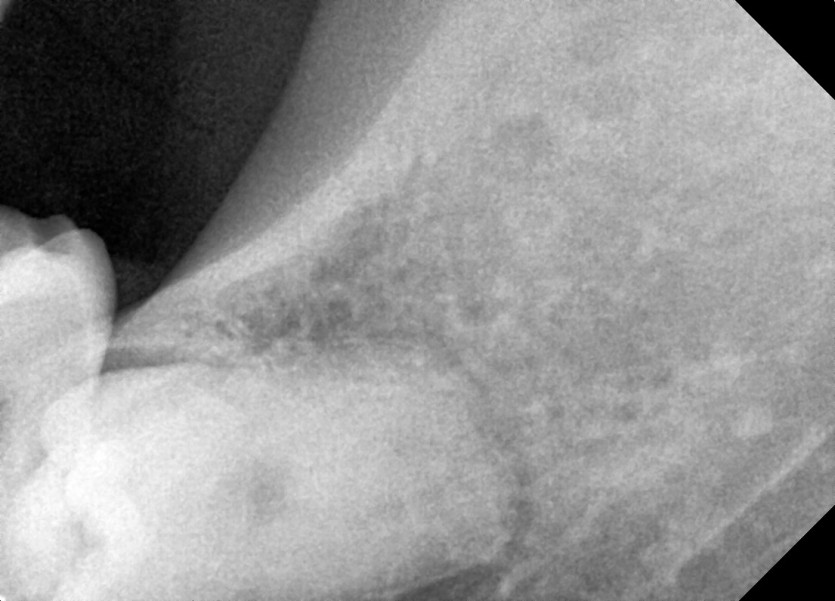

#28,38 사랑니 발치

구강 외과 전문의가 당일 발치했습니다.